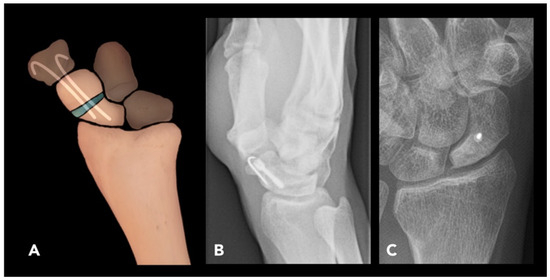

2.2.4. Scaphoid Corrective Osteotomy

- Trumble, T.E.; Gilbert, M.; Murray, L.W.; Smith, J.; McCallister, W.V. Displaced Scaphoid Fractures Treated with Open Reductio and Internal Fixation with a Cannulated Screw. JBJS 2000, 82, 633. [Google Scholar] [CrossRef]

- Kawamura, K.; Chung, K.C. Treatment of scaphoid fractures and nonunions. J. Hand Surg. 2008, 33, 988–997. [Google Scholar] [CrossRef]

- El-Karef, E.A. Corrective osteotomy for symptomatic scaphoid malunion. Injury 2005, 36, 1440–1448. [Google Scholar] [CrossRef] [PubMed]

- Buijze, G.; Bulstra, A.; Ho, P. Management of complications of scaphoid fracture fixation. In Management of Complications in Common Hand and Wrist Procedures: FESSH Instructional Course Book; Thieme Medical Pub: Stuttgart, Germany, 2021; Volume 1, pp. 89–104. [Google Scholar]